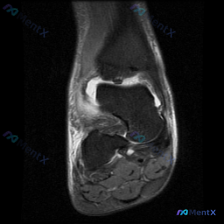

这是一份踝关节MRI冠状位T2加权图像,整理核心影像发现如下:

- 骨骼系统:胫骨远端、距骨骨皮质连续性无中断,骨髓腔无明显弥漫性高信号,无明确急性骨髓水肿或骨挫伤

- 关节与软骨:胫距关节间隙可见明显高信号,提示关节积液;距骨穹窿关节软骨面轮廓欠平整,距骨穹窿内侧关节面边缘可见异常信号,软骨下骨存在局限性信号异常

- 韧带软组织:内侧三角韧带结构模糊伴信号增高,外侧韧带复合体信号混杂轮廓不清,提示损伤伴周围软组织水肿;踝关节周围弥漫性斑片状T2高信号,符合广泛软组织水肿